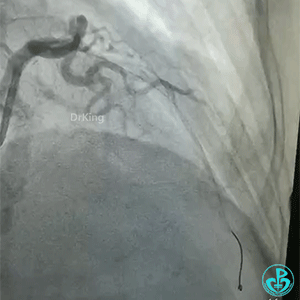

导丝怎么扩真怪!急性心梗前降支导丝通过顺利,球囊扩张后导丝移位很多!不在原来的血管腔!_https://www.jmylbn.com_新闻资讯_第3张

再进一根导丝,可以在对角支和主支随意进出,随后病人血流变慢,症状有加重,后面的造影血流更慢。